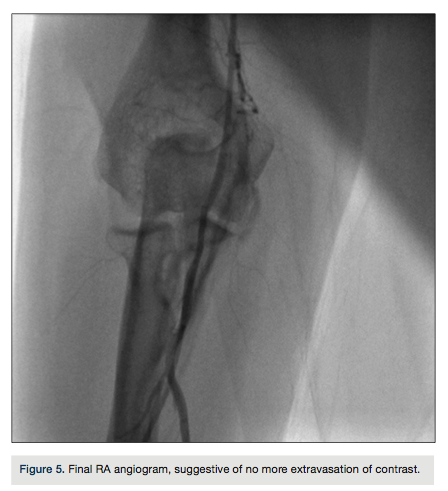

A RA arteriogram at the completion of the procedure showed no extravasation of contrast (Figure 5). A hemostatic transparent band was applied at the radial access site for 1 hour while following a patent hemostasis protocol. The patient did not have a hematoma or residual local pain. The patient was re-evaluated with a reverse Allen’s test on the thirtieth day after the procedure with evidence of intact RA flow.